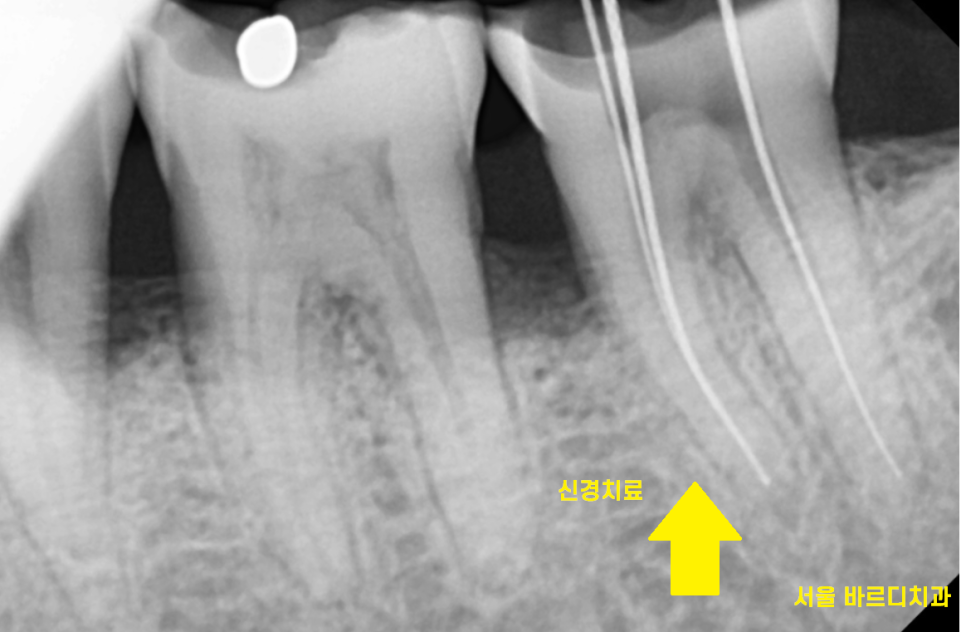

22.05.11

신경치료의 마무리는

보철을 씌우는 것으로 마무리됩니다.

신경을 제거하고나면

내부가 텅 비게 되는데

한마디로 텅빈 강정이 되어버립니다.

치아는 신경을 통해

영양분을 공급받는데

신경치료를 받게되면

신경을 제거하면서

영양공급이 끊겨버리기 때문이죠~!

신경치료 후 보철을 씌워주는 이유는

치아를 보호해주기 위해서인데요.

23.10.16

결국 이가 반으로 갈라져서

환자분은 발치 후 임플란트 치료를 진행하셨답니다.